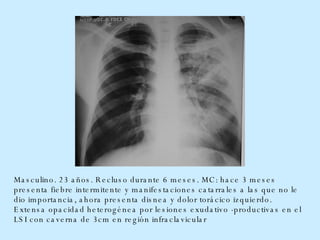

Masculino. 23 años. Recluso durante 6 meses. MC: hace 3 meses presenta fiebre intermitente y manifestaciones catarrales a las que no le dio importancia, ahora presenta disnea y dolor torácico izquierdo. Extensa opacidad heterogénea por lesiones exudativo -productivas en el LSI con caverna   de 3cm en región infraclavicular

Masculino. 23 años. Reclusodurante 6 meses. MC: hace 3 meses presenta fiebre intermitente y manifestaciones catarrales a las que no le dio importancia, ahora presenta disnea y dolor torácico izquierdo. Extensa opacidad heterogénea por lesiones exudativo -productivas en el LSI con caverna de 3cm en región infraclavicular